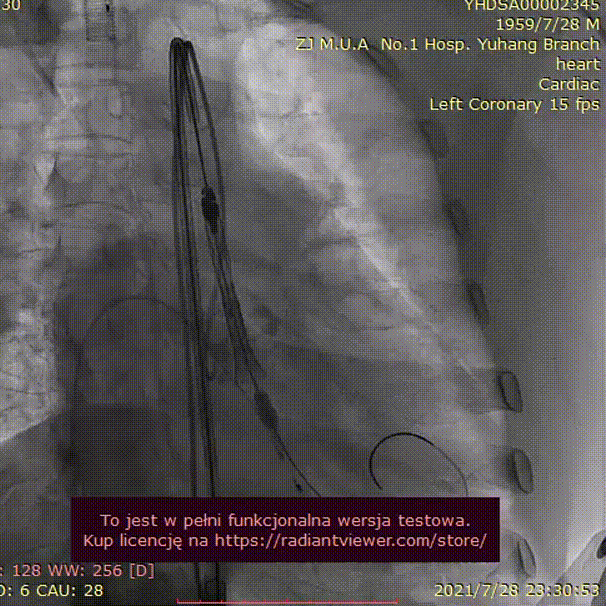

手术过程:

23mm球囊预扩

(有腰征,无瓣周漏,右冠开口阻塞)

TAV24 瓣膜释放前定位

释放4.0*30mm烟囱支架

植入后造影

术后压差1mmHg

术中经食道心超评估: